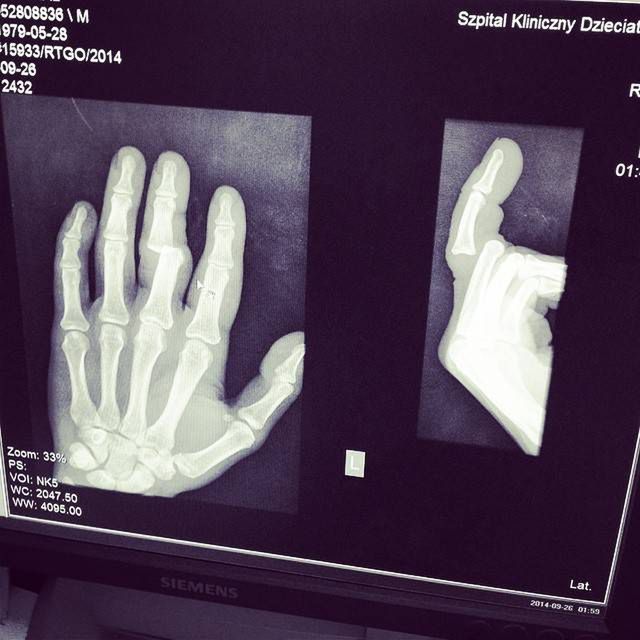

Złamanie wygląda paskudnie. Kość jest zupełnie odczepiona od reszty struktury kości palca. Na pewno będzie się bardzo długo goić. Wszyscy bardzo współczują Michałowi. Teraz nie będzie mógł ani tańczyć, ani nadwyrężać ręki także przy codziennych czynnościach. Na szczęście to lewa ręka - oczywiście to dobra wiadomość, tylko wtedy, jeśli Michał nie jest leworęczny. Mamy nadzieje, że do wesela się zagoi (zobacz: Michał Piróg się żeni? To zdjęcie może o tym świadczyć).

Poniżej prześwietlenie RTG ręki Michała.

Ręka Michała Piróga